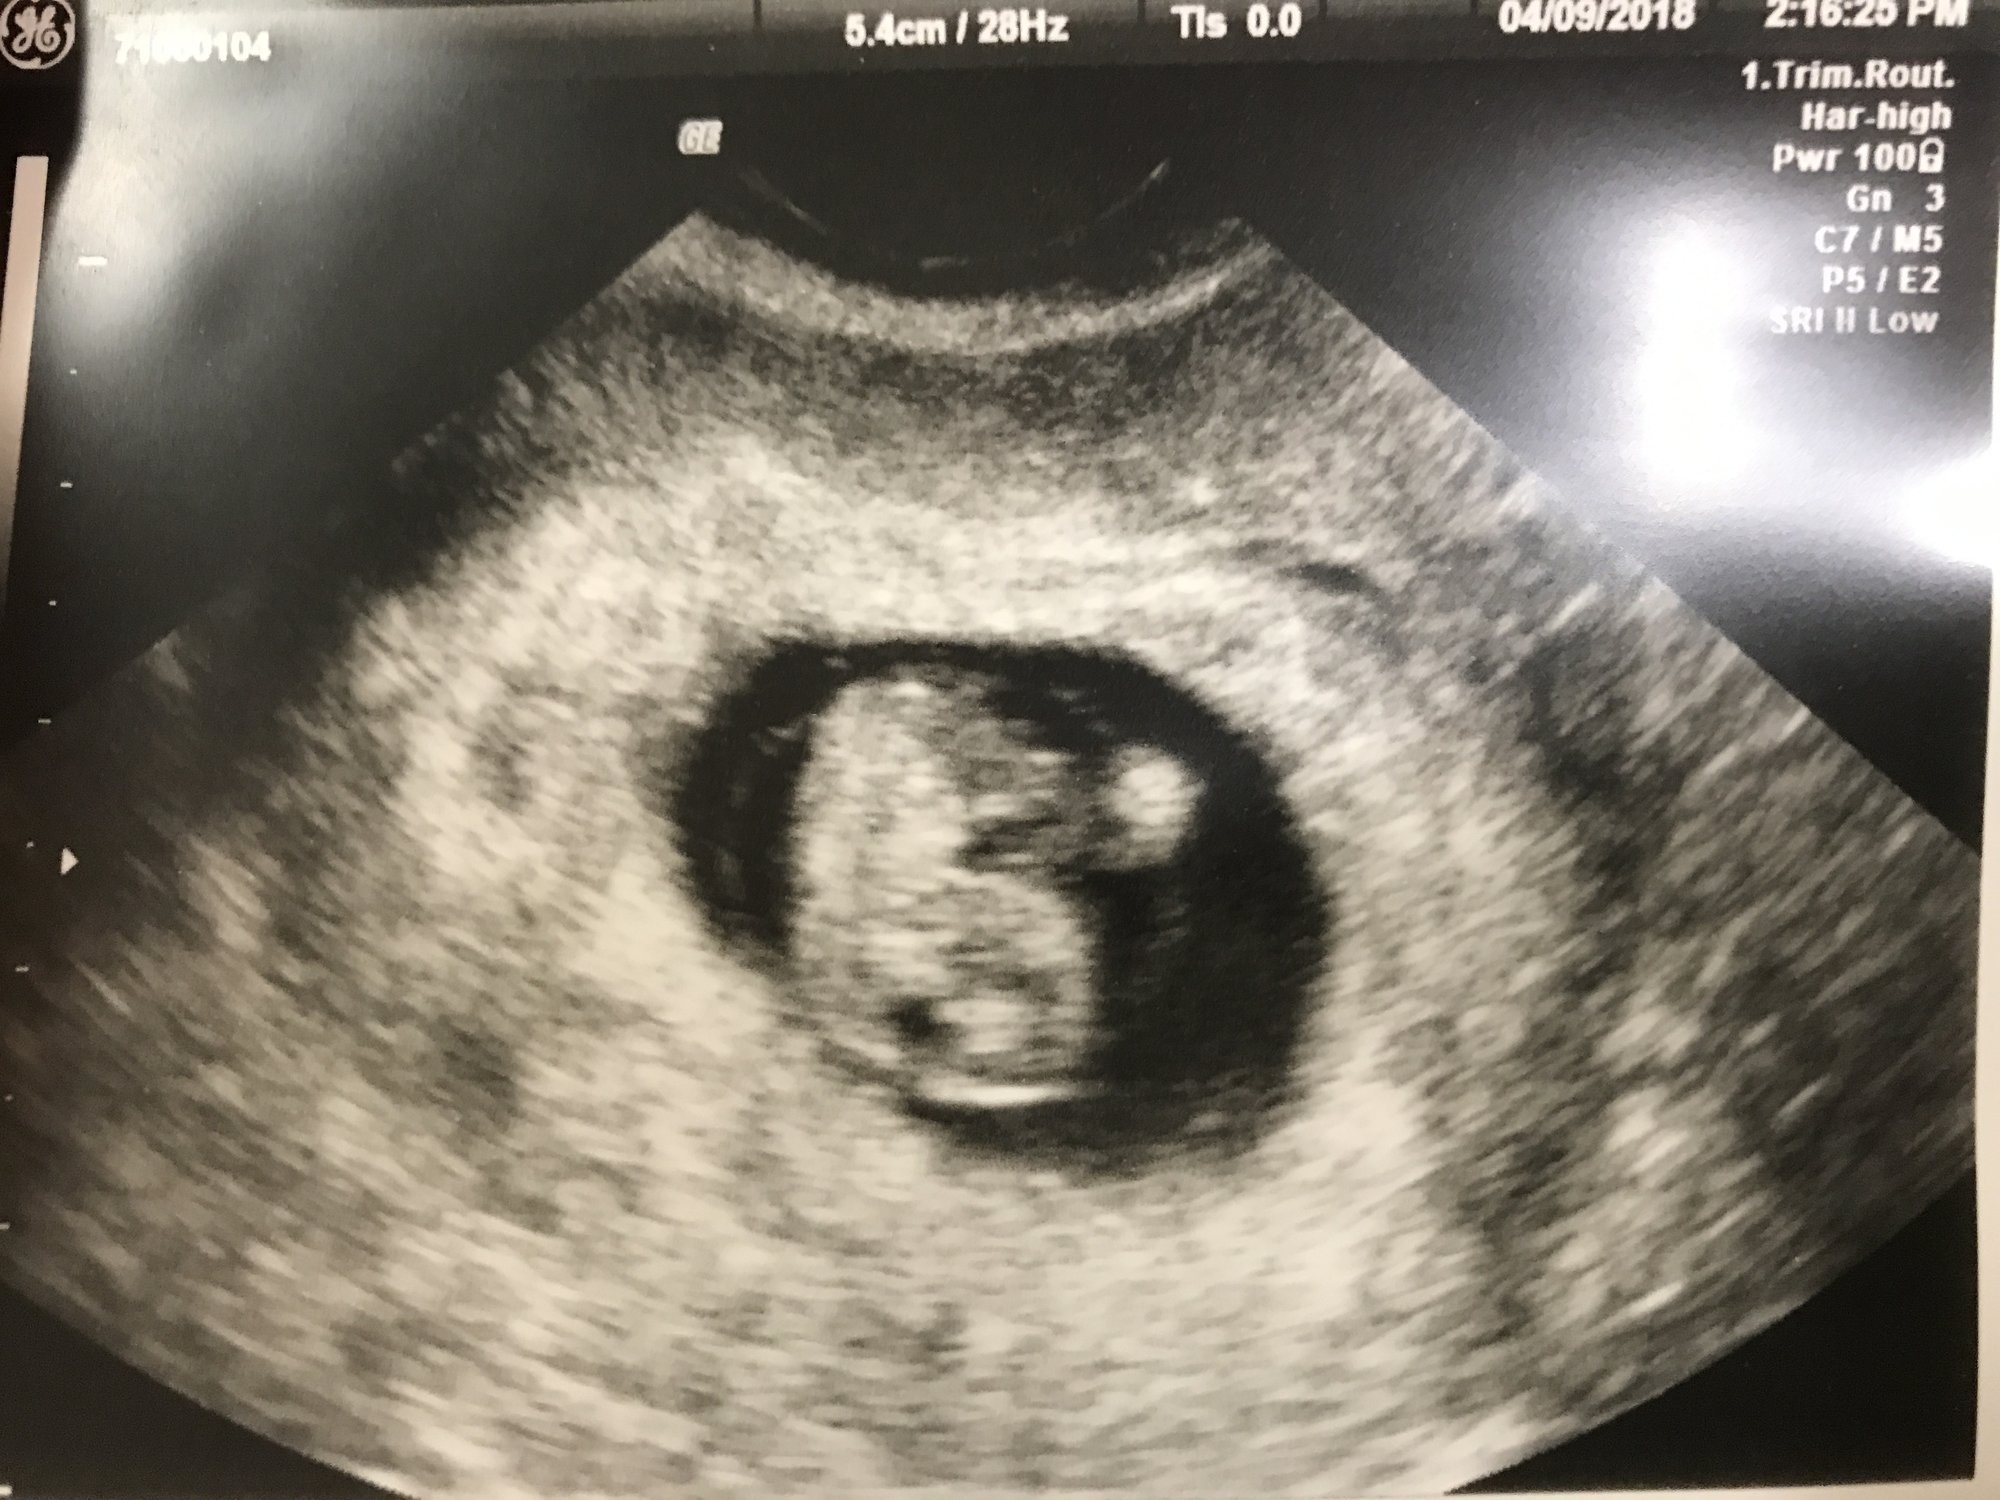

• I had my first ultrasound on Monday! I'm not as far along as I thought - I thought I was past 10 weeks but I'll be just 10 weeks tomorrow. So glad I decided to have an early ultrasound - last pregnancy I just had one at 20 weeks. This time around I was having cramping and bleeding and something seemed off. I guess this is why!!!! Seeing double!! They think identical but can't quite be certain yet as I only wanted an abdominal ultrasound this visit. Needless to say I'm freaking out! New due date of November 8th instead of the 3rd...but I'm sure with twins it may be October!

Holy cow, identical twins!! Congratulations! The hospitals I've worked at deliver identical twins no later than 36 weeks (which I believe is the recommendation) due to the increased risks if you go past that. FX for a smooth pregnancy for you!